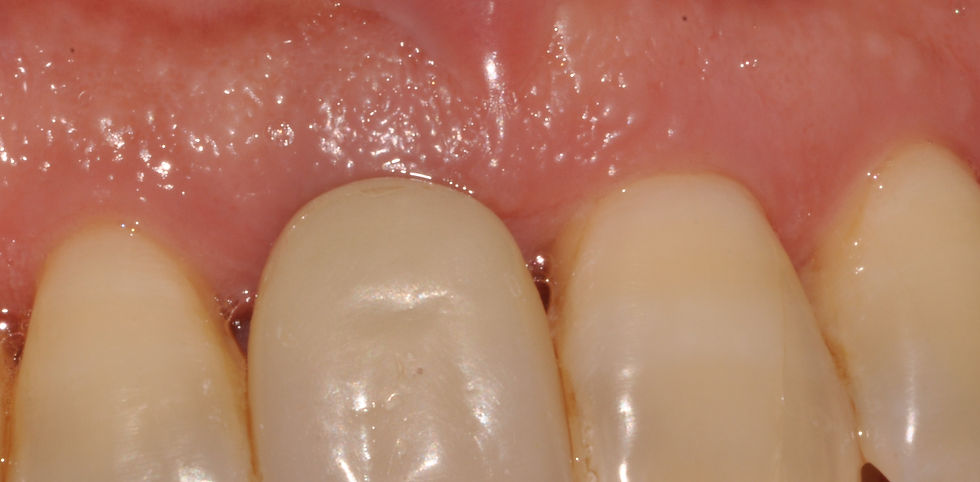

Patient of 46 years in apparent good health, non-smoker, periodontal disease in maintenance, arrives under our observation for a preternatural mobility of 1.1, reporting a trauma on this element. The intraoral inspection shows third degree mobility and the radiographic examination shows a fracture of the apical third of this element. In agreement with the patient, the tooth and the fractured fragment were extracted and an immediate post-extraction implant with immediate loading was performed, after exposing the risks of this procedure. After the atraumatic extraction, also the apical fragment was extracted and a PRAMA 3.8x13 implant was inserted, obtaining a primary stability of 70N. An immediate provisional restoration of this implant was carried out with a commercially available post which was adapted for this purpose; the healing times were awaited as described on the captions to images. We proceeded to the optical impression and in this phase we realized that there was a fragment of temporary cement left on the gum, leaving an impression on it. During the optical impression, we were able to note how the gum, once the fragment of cement has been removed, perfectly adapted on the crown profile and restored. We then proceeded to a second individualized provisional restoration, made by Sweden & Martina cad-cam center, on a customized post. During the following weeks, the emergence profile of the provisional restoration was then adapted to obtain a gingival scallop as natural as possible, in accordance with the subject's periodontal disease. A laser melting and ceramic crown was then delivered to the patient, then monitored with regular follow up controls.